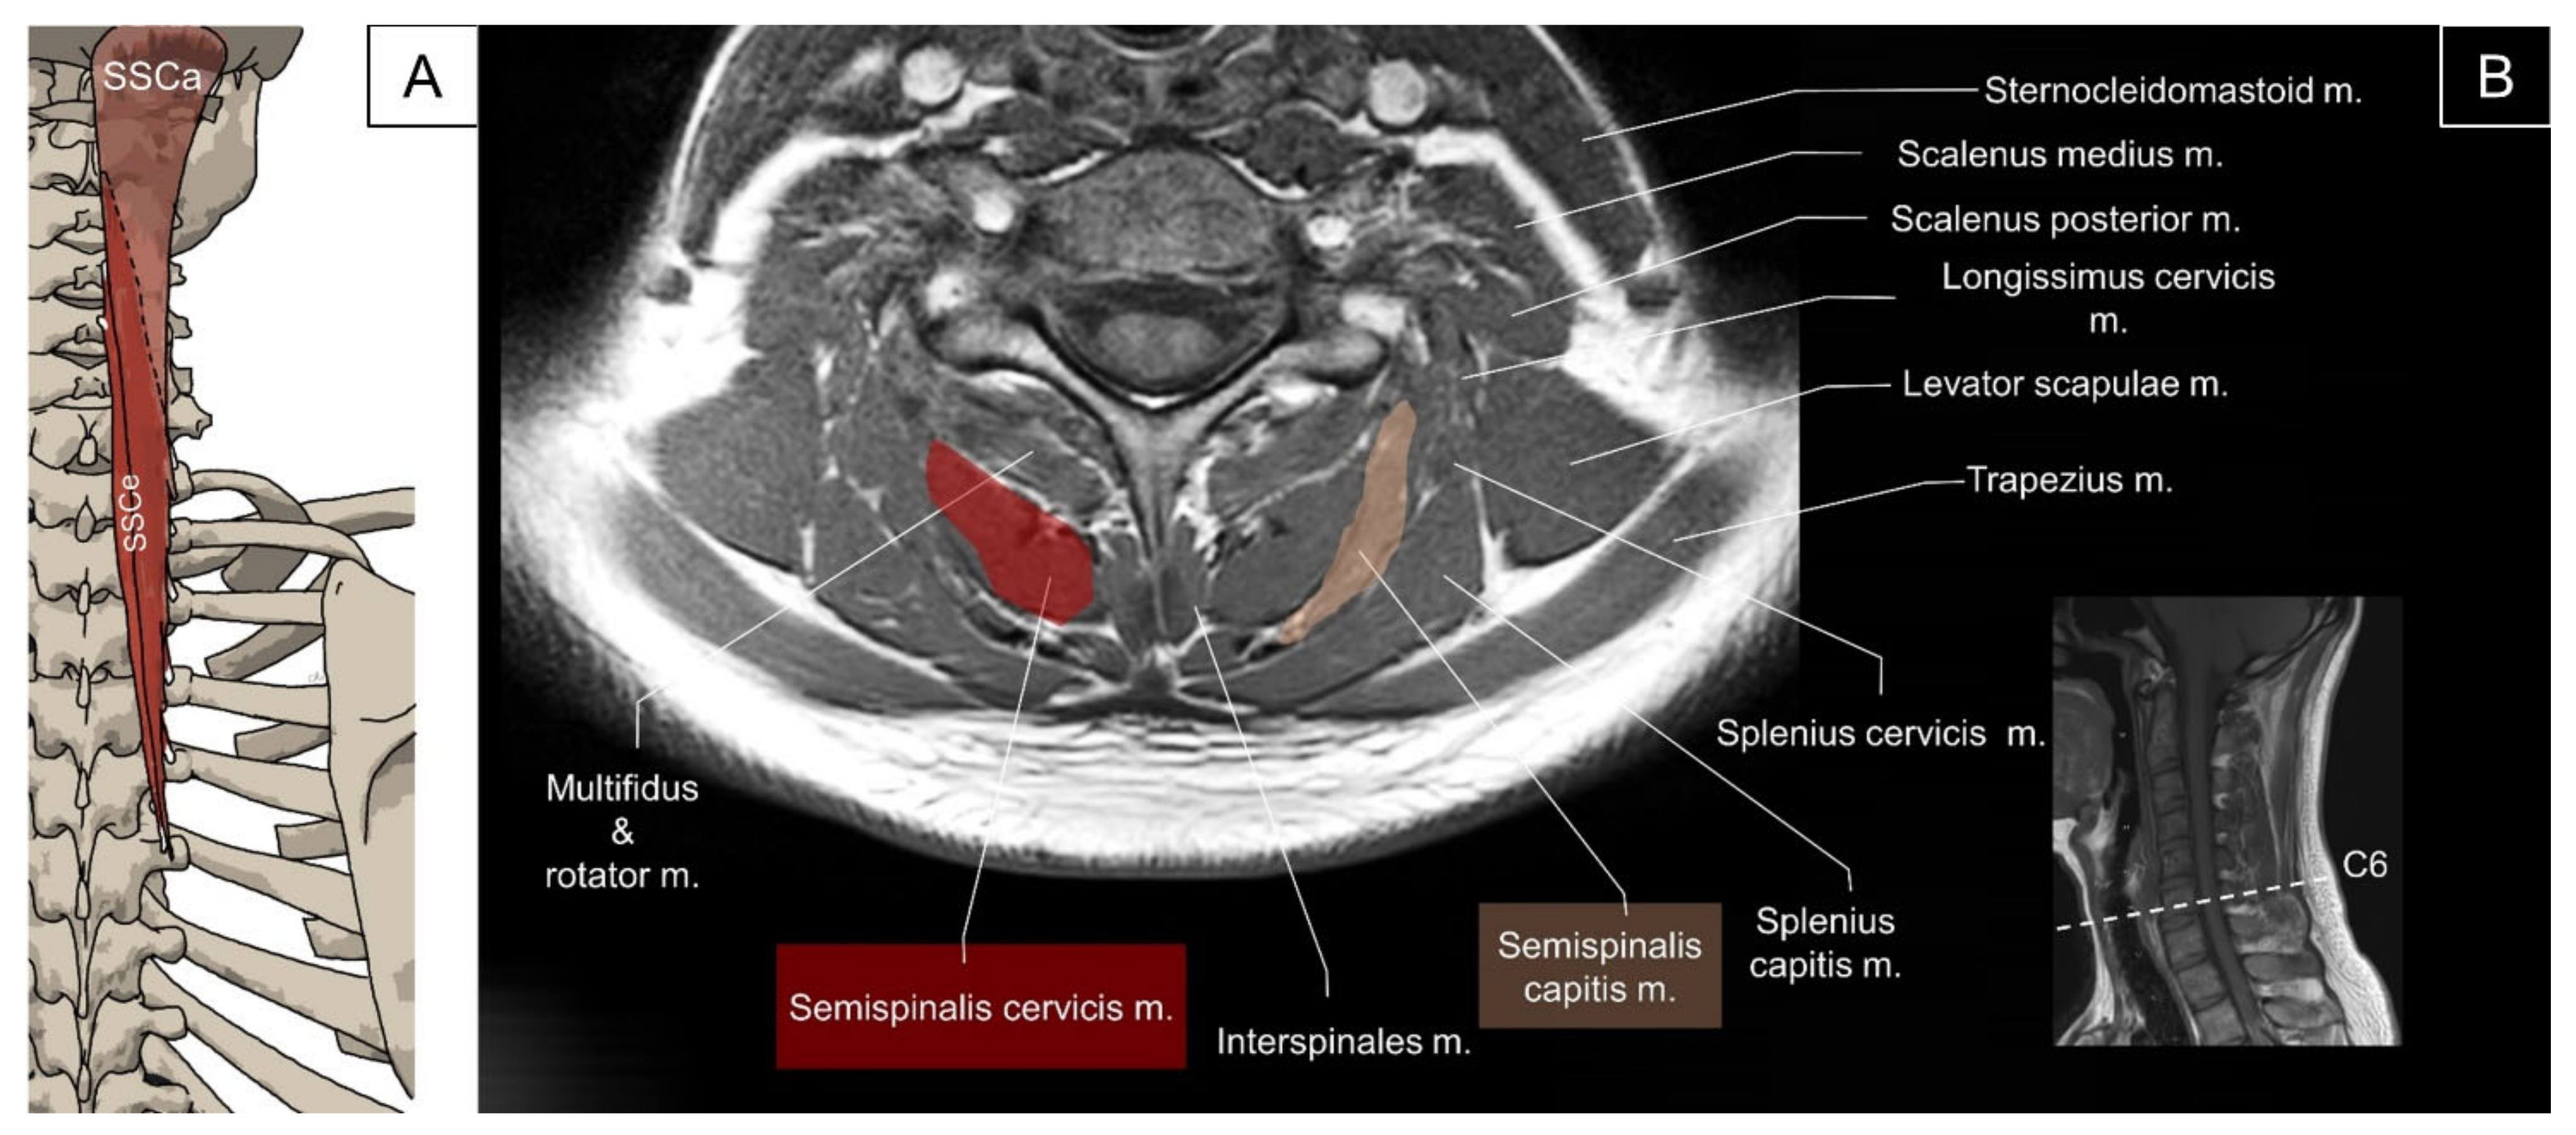

4.3. Transversospinalis (Semispinalis Capitis/Semispinalis Cervicis/Multifidus)

4.3.1. Anatomy

4.3.2. Sonographic Scanning

4.3.3. Clinical Relevance